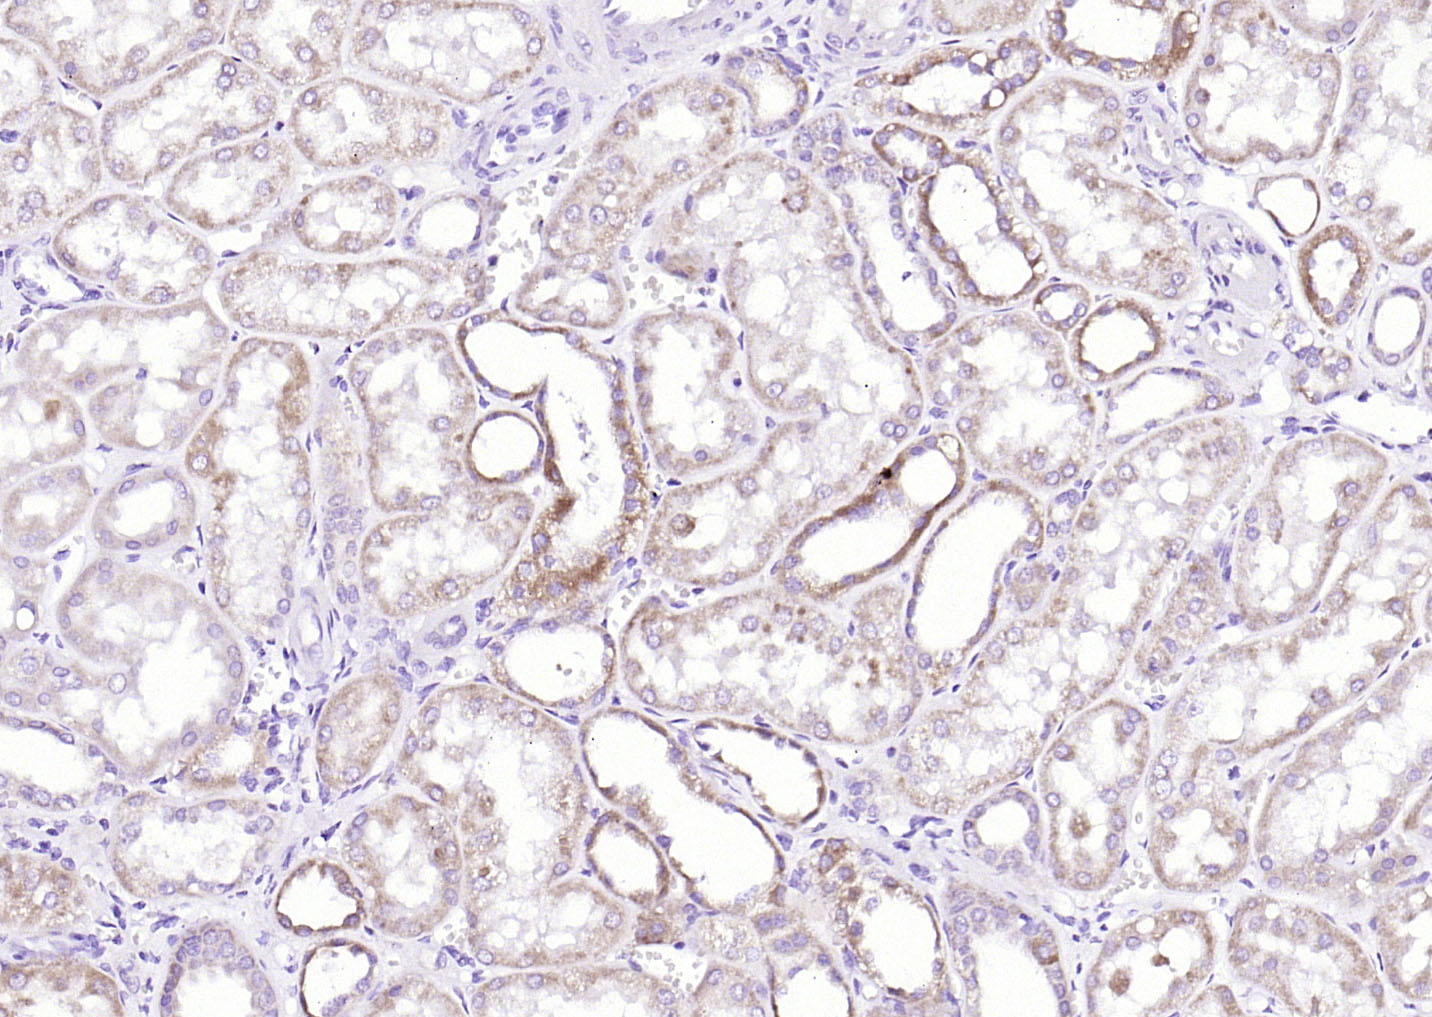

Paraformaldehyde-fixed, paraffin embedded (Human kidney); Antigen retrieval by boiling in sodium citrate buffer (pH6.0) for 15min; Block endogenous peroxidase by 3% hydrogen peroxide for 20 minutes; Blocking buffer (normal goat serum) at 37°C for 30min; A